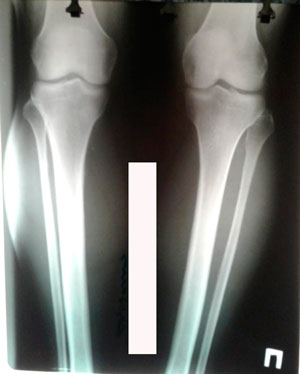

Дата операции - 13.03.2020

Дата снятия аппаратов - 26.06.2020

Вложения

image-26-06-20-12-40-1.jpg

image-26-06-20-12-40.jpg